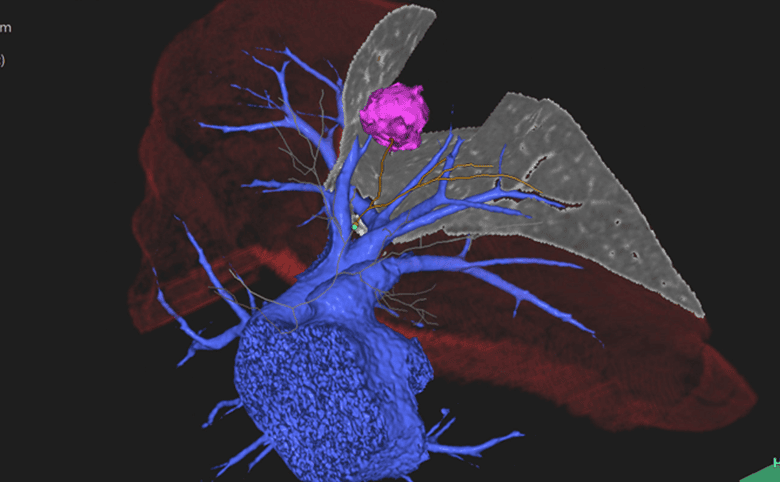

Reconstructions 3D

De quoi s’agit-il ?

Nous reconstruisons l’anatomie du patient en 3 dimensions grâce à un scanner thoracique (en utilisant le logiciel Synapse 3D) avant l’opération afin de la préparer car chaque patient est unique et chaque anatomie est différente.

A quoi ça sert ?

Les reconstructions 3D permettent au chirurgien de :

- diminuer la durée de l’intervention chirurgicale grâce à un gain de temps de dissection

- planifier le déroulé de l’intervention chirurgicale, c’est-à-dire , prévoir les étapes de dissection de l’organe

- réaliser des interventions plus complexes qu’auparavant grâce à une meilleure précision de la connaissance de l’anatomie du patient qui est soigné

- diminuer le risque d’erreur anatomique pendant l’opération quand les patients ont une anatomie inhabituelle

- diminuer le risque d’accident hémorragique lors de l’intervention

- améliorer les marges de résection de sécurité d’une tumeur en augmentant ainsi la qualité oncologique du geste